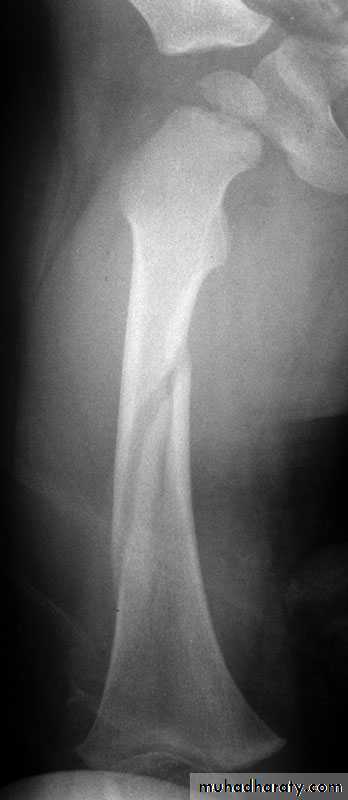

8Types

Transverse : tension or direct force

Butterfly fragment : bending

Short oblique : compression

Long oblique : indirect force

Spiral : twisting